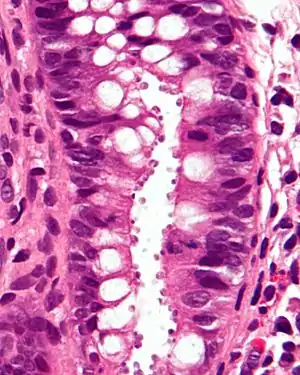

| Micrograph showing cryptosporidiosis. The cryptosporidium are the small, round bodies in apical vacuoles on the surface of the epithelium. H&E stain. Colonic biopsy. | |

Other staining techniques include acid-fast staining,[33] which will stain the oocysts red.[32] One type of acid-fast stain is the Kinyoun stain.[27] Giemsa staining can also be performed.[28] Part of the small intestine can be stained with hematoxylin and eosin (H & E), which will show oocysts attached to the epithelial cells.[32]